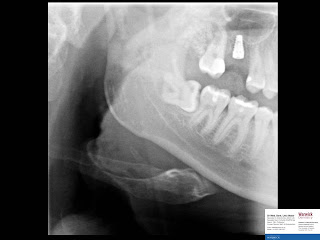

Internal sinus elevation - immediate implant placement - socket grafting